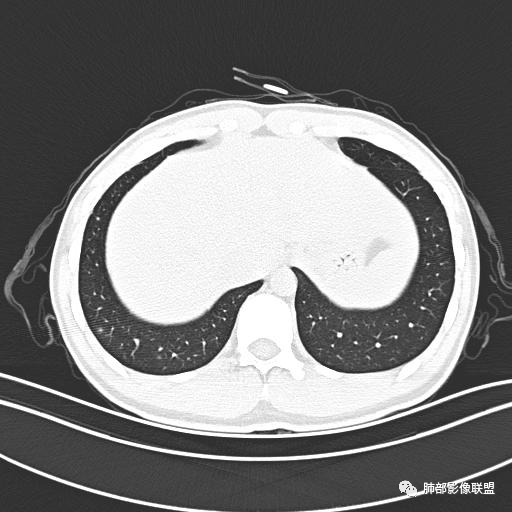

小强:青年,发热,皮疹;双肺散在结节,周围磨玻璃,点晕征,疱疹病毒感染,鉴别荚膜组织胞浆菌,结核。 大雄:青年,急性起病,发热伴全身皮疹2天,抗病毒治疗体温有下降。双肺随机分布大小不等类圆结节,“点晕征”。考虑水痘-疱疹病毒(VZV)血播询问接触史,查体皮疹分布以及形态基本可诊断。 王开金江津中心医院呼吸科:青年男性,起病急,病程短,以发热,皮疹为首发症状,感染指标以单核细胞升高为主,胸部ct双肺多发结界,周围有晕,点晕表现,随机分布,同意於老师意见,水痘疱疹病毒血流感染累及肺。 王秀仙:双肺多发大小不等结节,周围有晕,边缘模糊,呈点晕征表现。青年,急性起病,发热伴全身皮疹2天,抗病毒治疗体温有下降。考虑疱疹病毒。鉴别荚膜组织胞浆菌。 傅昌瑜:19岁男性,发热、全身皮疹2天,单核细胞增高,双肺多发结节,结节边缘见边界不清磨玻璃影。点晕征+发热、全身皮疹+单核细胞增高——考虑水痘-带状疱疹病毒肺炎。 一切∮随缘:年轻男性,发热,皮疹两天,实验室,CRP,PCT增高,影像:双肺多发散在磨玻璃结节,边界欠清,大小不等,呈点晕征改变,以血管束周围分布为主,局部血管束略增粗,其它无明显改变,考虑:1:病毒性肺炎(水痘疱疹病毒?不知道皮肤有无改变)2:真菌(组织胞浆菌,血管侵袭性肺曲霉)3:GPA4:寄生虫(实验室没有看到嗜酸细胞增高) 赵山河:双肺散在结节,周围有晕,边缘模糊,呈点晕征表现。青年,急性起病,发热伴全身皮疹2天,抗病毒治疗体温有下降。考虑水痘—疱疹病毒感染。洪桥爱:青年男性,发热、皮疹2天,伴瘙痒,皮疹于面部首发,之后进展至全身,虽然没有对皮疹进行描述,但是从出疹时间及皮疹进展情况,伴瘙痒,应该就是个水痘患者;CT提示双肺随机分布结节影,部分结节伴有边界不清晕征,考虑水痘血播肺。 刘强:年轻男性,急性起病,皮疹,发热,抗感染治疗体温下降,说明有效。影像表现为散在点晕征,感染类疾病谱(疱疹病毒,真菌,结核),结合年龄,皮肤皮疹,考虑水痘-疱疹病毒性肺炎。 小兜:男性,19岁,发热皮疹两天,颜面部至全身,CRP,降钙素及单核增高。CT示双肺散在小结节,周围伴磨玻璃影,点晕征,考虑为水痘-带状疱疹病毒(varicella-zoster virus,VZV)肺炎 必有路:青年,皮疹+发热+“点晕征”→水痘-疱疹病毒(VZV) 许慧良:青年男性患者,发热、皮疹2天,体温最高38.5℃,第3天皮疹扩展至全身,伴瘙痒,胸部CT:双肺多发随机分布的小结节,结节周边见边界模糊的晕征,考虑水痘病毒感染流心明智:男,19,急性起病,发热伴全身皮疹2天。出疹顺序头→全身,抗病毒有效。胸部CT:两肺多发大小不等类圆形实性小结节影,随机分布,结节周围环绕GGO,边界模糊,呈点晕征。出疹特点是关键,未提示。考虑:血播病毒性肺炎,水痘-疱疹病毒?麻疹?鉴别荚膜组织胞浆菌、TB、血管炎、寄生虫等。 浪迹天涯:病灶多为5-10mm大小结节,结节周围可见磨玻璃样的晕环,常多发,可分布于肺内任何区域,考虑水痘—带状疱疹病肺炎如果短时间内有新的一个区域浸润,更加能说明,